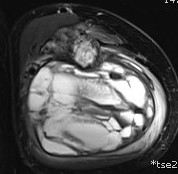

MRI

Evaluate

i) Soft tissue component

ii) Involvement of neurovascular bundle

iii) Marrow extent of tumour

- helpful in determining appropriate resection level

- satellite lesions - metastasis within reactive zone

iv) Identify skip lesions

- metastasis outside reactive zone

- sagittal and coronal images of the entire bone

v) Joint involvement